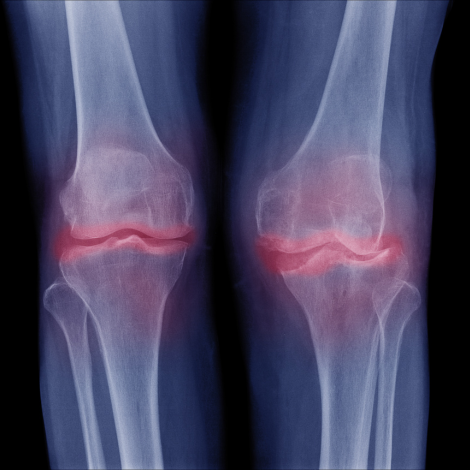

Knee X-ray

Your healthcare provider may use a knee X-ray to diagnose possible health and medical conditions in your knee or knees. Knee X-rays can show signs of broken knee bones (fractures); joint dislocation; excess fluid, which can be a sign of a sprain; loose pieces of bone; bone spurs (osteophytes); osteoarthritis.